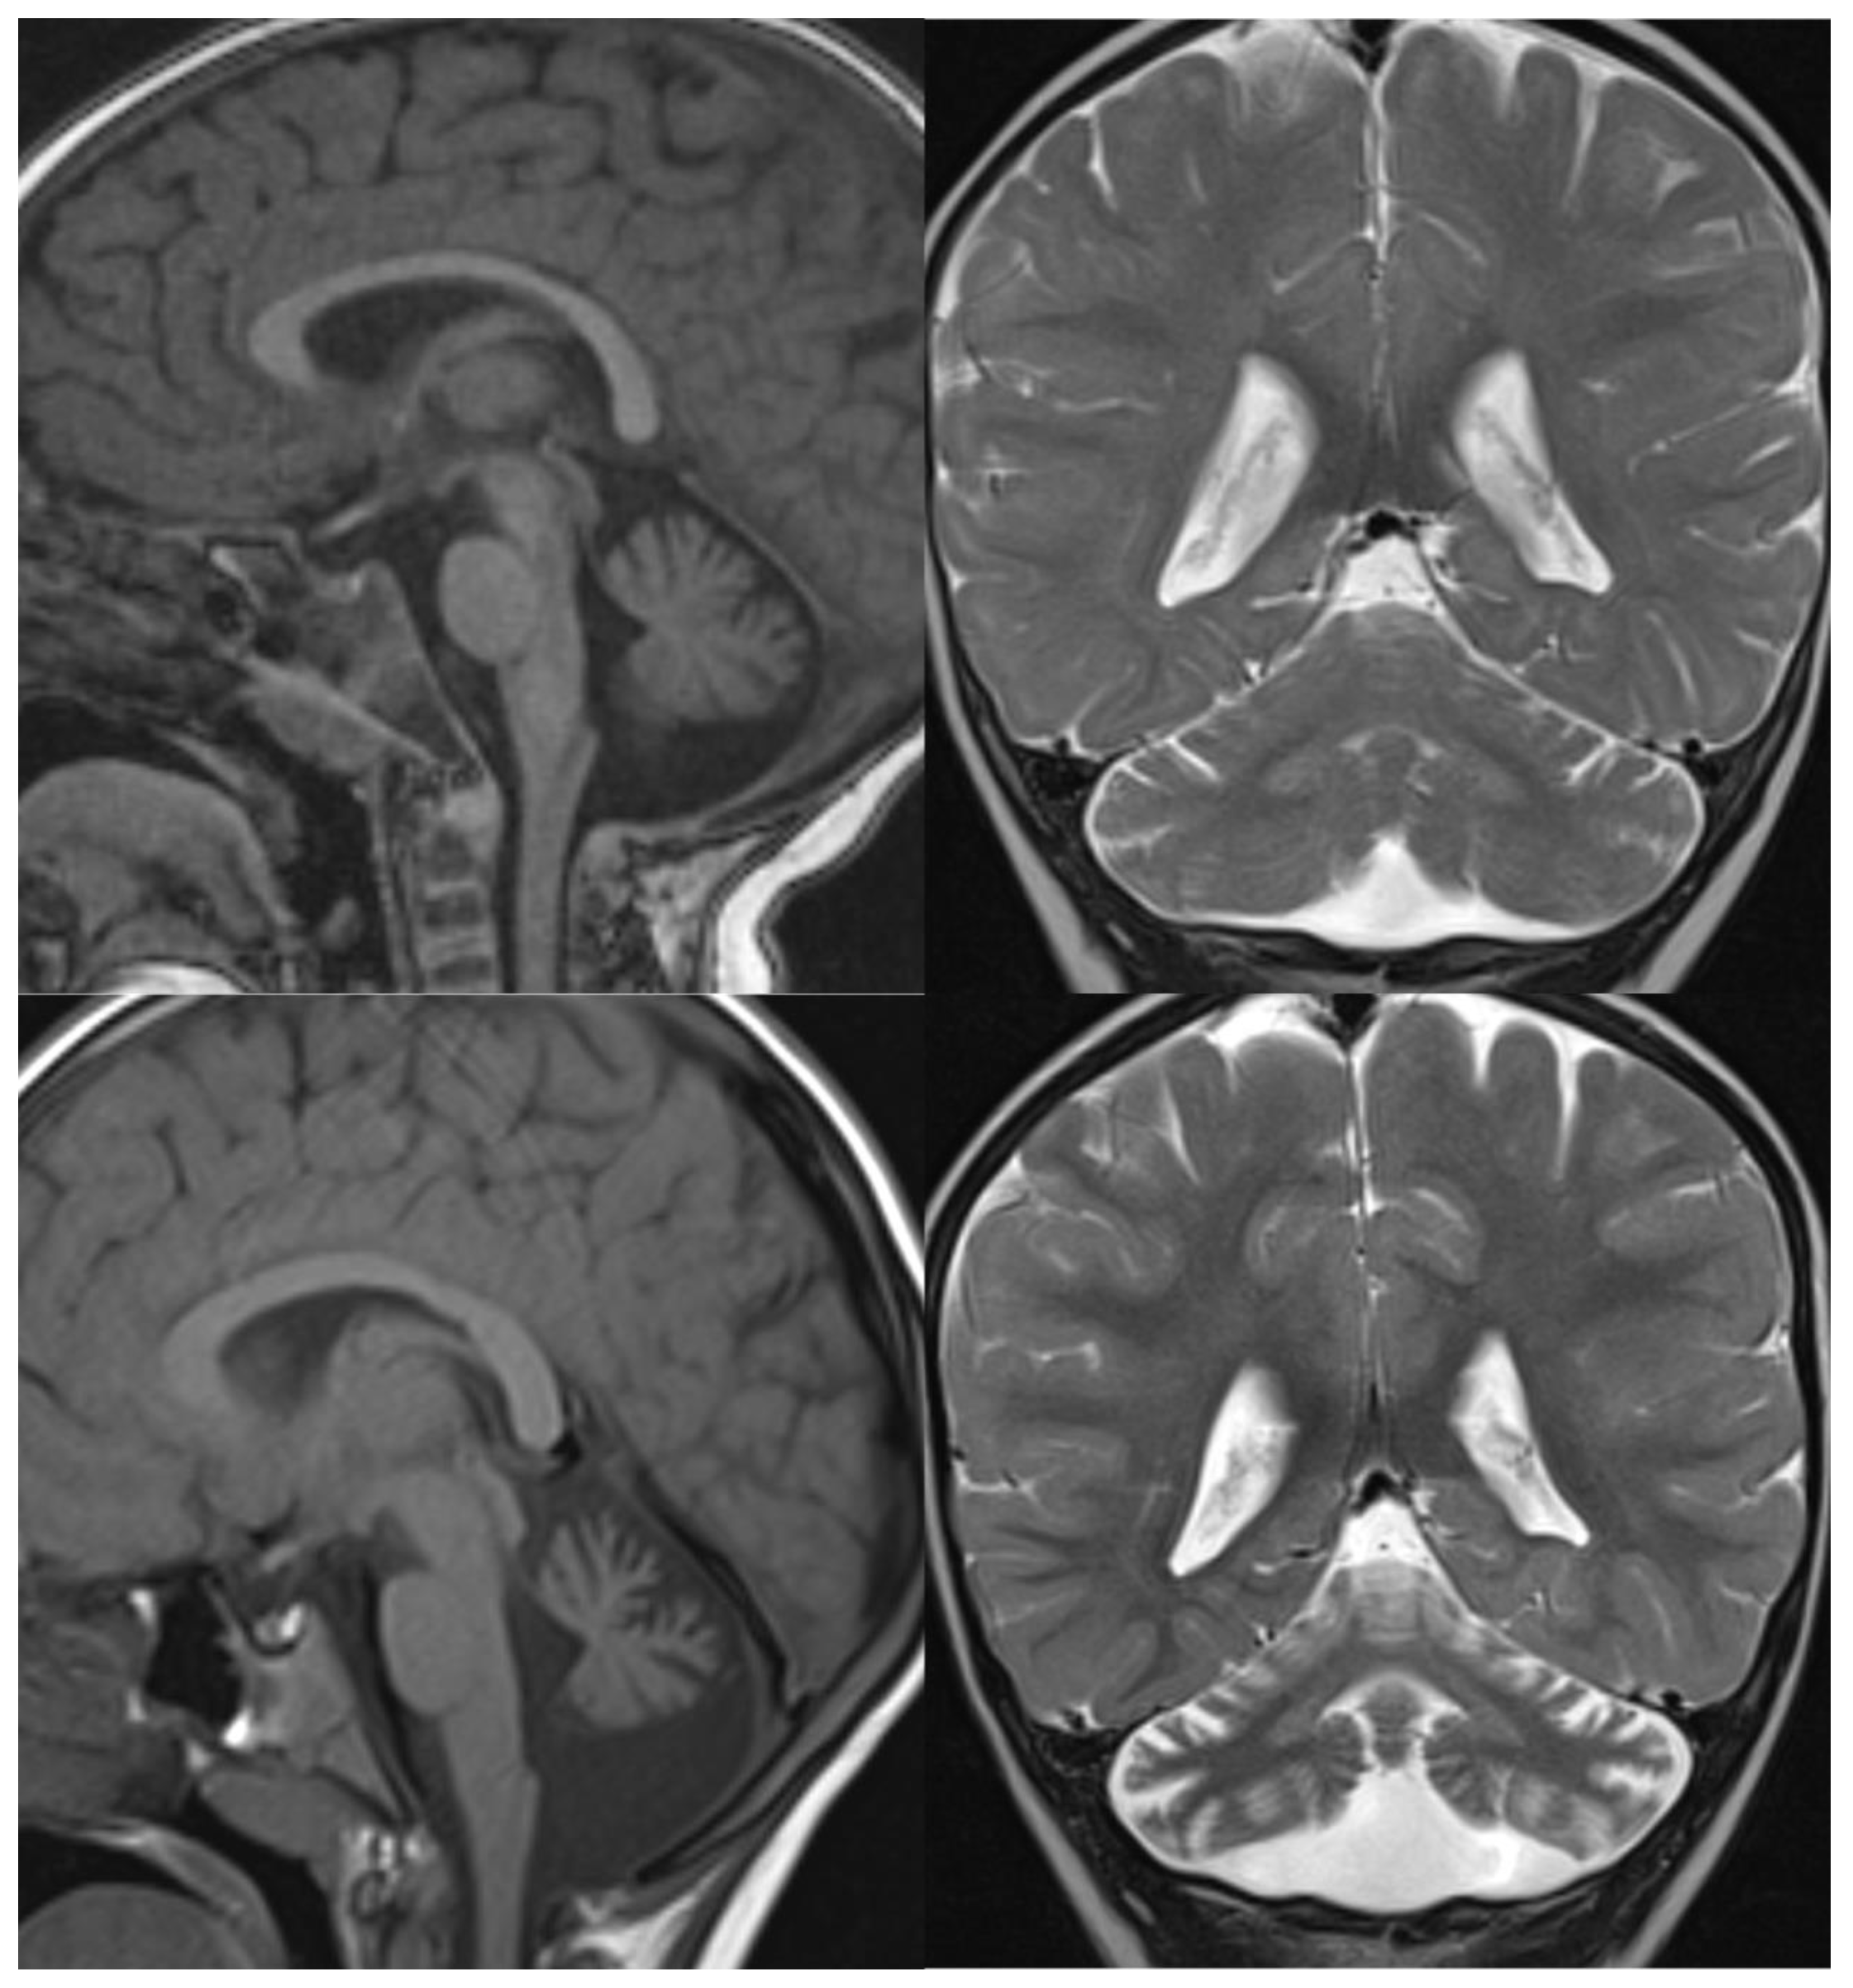

Overall, MRI in PCH patients shows a variable degree of cerebellar hypoplasia with involvement of pons and cerebrum. On coronal imaging, the particular shape of the cerebellum, named “dragonfly” or “butterfly” appearance, was described by Barth et al. [6]. The cerebellar hemispheres are particularly atrophic, with a substantial sparing of the vermis. Flattening of the caudate nuclear heads can be present [5]. Additional inconstant findings are cerebellar cysts (PCH 1, 2, and 6), agenesis of the corpus callosum (PCH 9), simplified gyral pattern (PCH 6 and 10), and hypomyelination (PCH 1, 2, 6, and 9). In several PCH, pons could be relatively preserved, and in PCH10, the cerebellum is mostly normal 11. The presence of C-shaped inferior olive has been reported in PCH2, suggesting a prenatal onset 9 (Figure 1).

Figure 1.

PCH 2. Brain MRI scan of a 1-year-old girl with TSEN 54 mutation. MR images demonstrate the characteristic “dragonfly-like” cerebellar pattern: severe hypoplasia of the cerebellar hemispheres with a relative sparing of the vermis. Note the flat ventral surface of the pons and thin corpus callosum.

Figure 2.

PCH6. Brain MRI scan of a 5-year-old boy. The size of the pons is almost normal, the vermis grossly diminished with enlarged interfolial spaces. Vermis and hemispheres are equally hypoplastic.